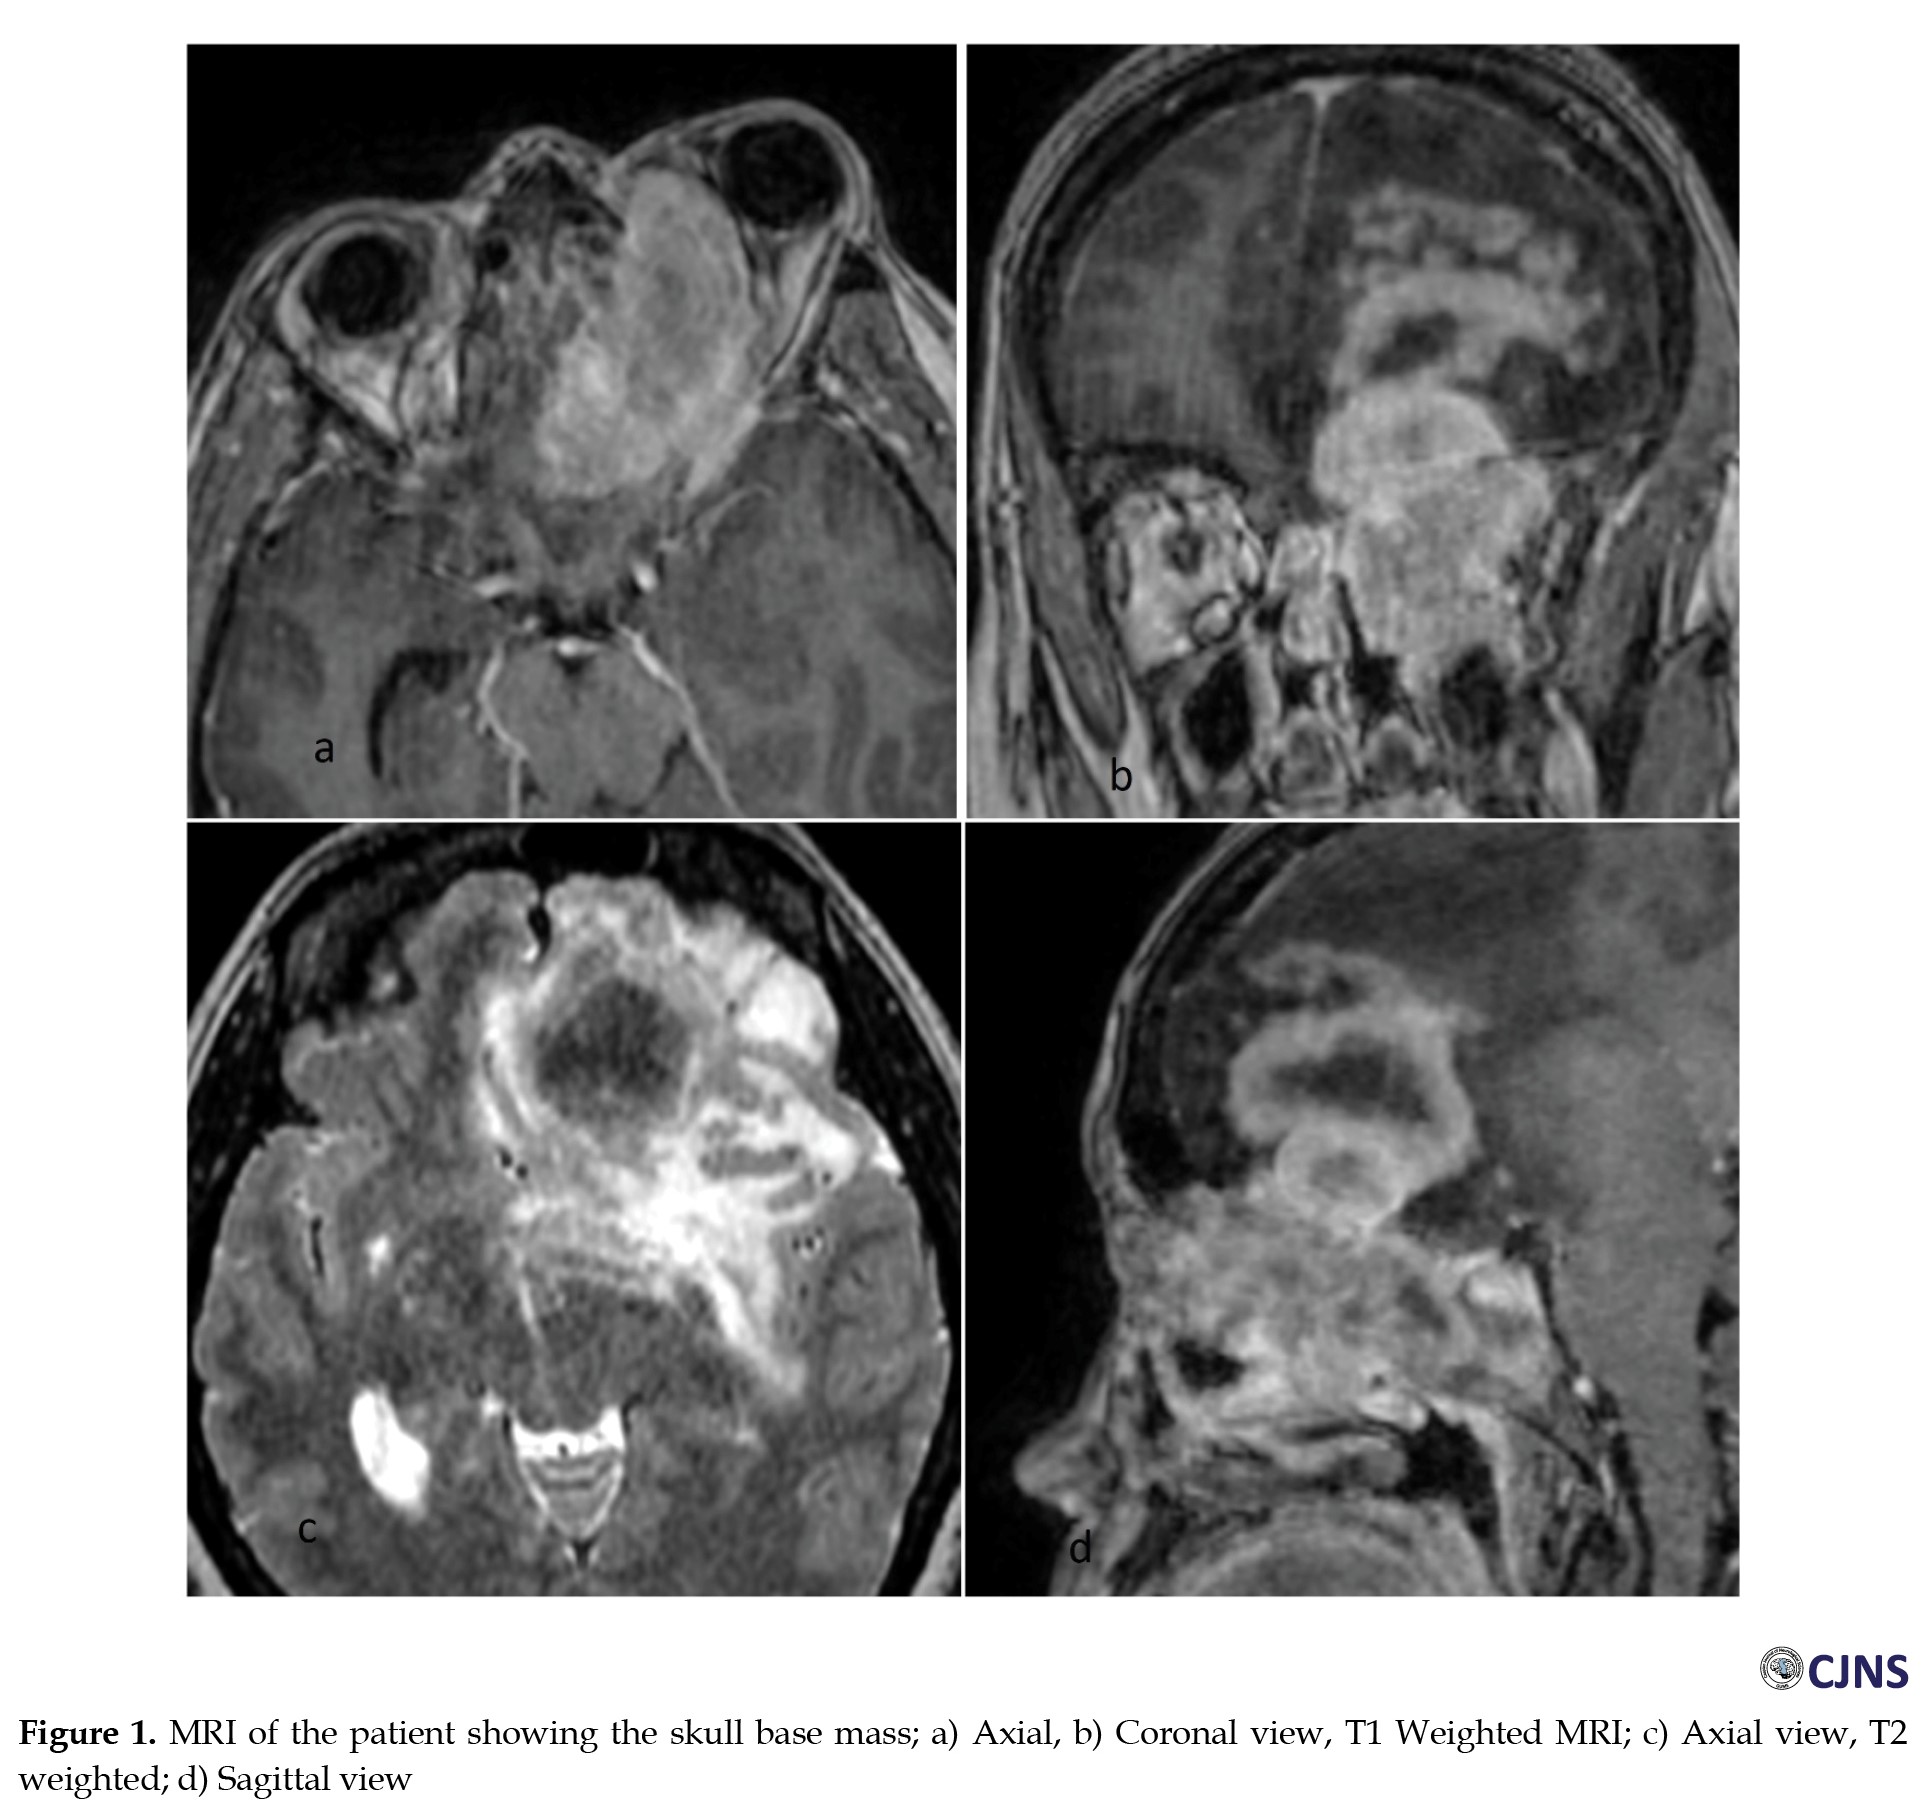

A 35-year-old woman was referred to our tertiary referral hospital in Tehran City, Iran, in January 2023 with a skull base tumor. She had presented with severe left eye proptosis and displacement of the eye globe to inferolateral since last year, which was insidiously progressing. She declared a history of asthma from childhood that was poorly controlled, although she seemed compliant with medical treatment. She had a history of intermittent oral corticosteroid use to manage asthma exacerbations in the past year. By the time of surgery, she was consuming steroid inhalers. On magnetic resonance imaging (MRI), a large soft tissue mass filled up the left ethmoid and sphenoid sinus cavities with extensive extension into the intracranial cavity and left orbit. There was also remarkable edema in the surrounding left hemisphere of the brain, with little shift from the midline to the right due to brain edema and limited central necrosis (Figure 1).